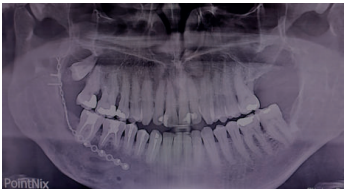

Su aspecto radiológico se caracteriza por una imagen radiotransparente, circunscrita unilocular, bien delimitada y en su interior suele contener la corona de un diente retenido 1-3. Sin embargo, la exploración radiográfica nunca nos permitirá hacer un diagnóstico diferencial con otras entidades como el queratoquiste o con tumores de potencial de crecimiento mucho más agresivo, como el ameloblastoma uniquístico. Por este motivo, quedaría desaconsejada la actitud expectante1,2,4,7 .

Acudió a servicio de cirugía oral, derivado por su odontólogo, un paciente varón de 65 años sin antecedentes médicos de interés, tras comprobar un importante crecimiento de una imagen radiotransparente respecto a última radiografía de hacía 5 años. El paciente no refirió sintomatología asociada. A la exploración extraoral no se apreció ningún tipo de deformidad ni afectación ganglionar. A la exploración intraoral pese a que se constató la integridad de las corticales, las cuales no estaban abombadas, sí que se pudo apreciar a la palpación un signo positivo de Dupuytren o de “Ping-Pong”. Además se constató una falta de afectación de los dientes del cuarto cuadrante que no presentaban movilidad y tenían una vitalidad positiva (Figura 1). Como complemento a la exploración clínica se solicitó un estudio mediante TAC, donde se apreció la extensión de una lesión radiotransparente que afectaba a rama y cuerpo mandibular derecho. (Figuras 2 y 3).